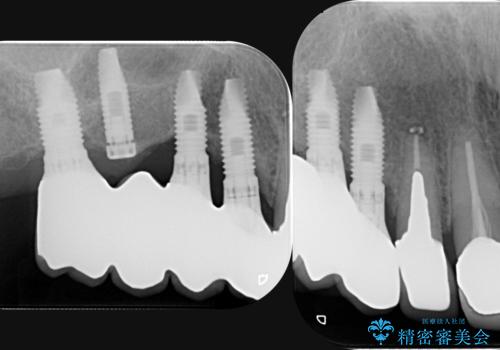

既に埋入されているインプラントは位置が悪いのでそのまま骨内に留置することとし、新たに咬合機能を回復すべく3本のインプラントを埋入すると同時に吸収した骨幅を増やし、安定してインプラントで噛める環境整備を目指します。

- 120万円(インプラント×3 チタンカスタムアバットメント×3 メタルボンドクラウン×3 骨造成 歯肉移植)費用は治療当時の料金となります

インプラントが長持ちするために、インプラント周囲の十分な骨量・角化歯肉の存在・安定した咬合を一つづつ整備する治療を行いました。